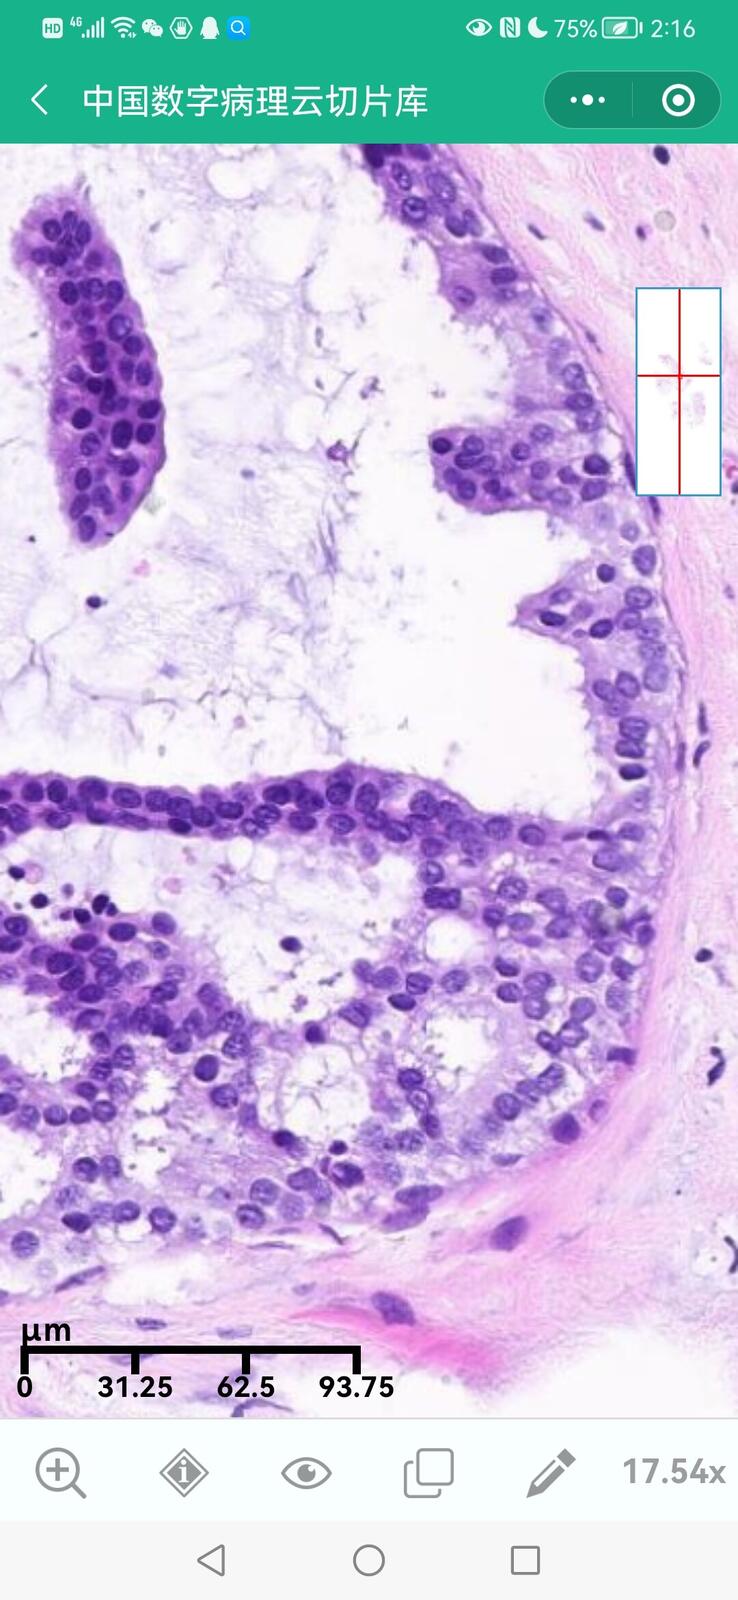

乳腺黏液性囊腺瘤伴导管内癌